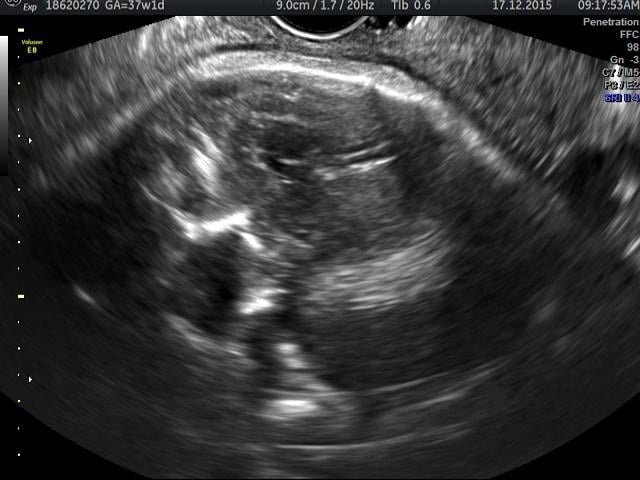

Below is a collection of prenatal ultrasound pictures from the Imaging Technology News (ITN) archive. Use the arrows to click through the image gallery. It includes transvaginal ultrasound images and fetal echocardiogram images. Fetal imaging is referred to by many names, including pregnancy sonograms, pregnancy ultrasound, endovaginal ultrasound, obstetric ultrasound, OB ultrasound, baby ultrasound, prenatal ultrasound. Fetal heart ultrasound is also called baby echo or prenatal echo.